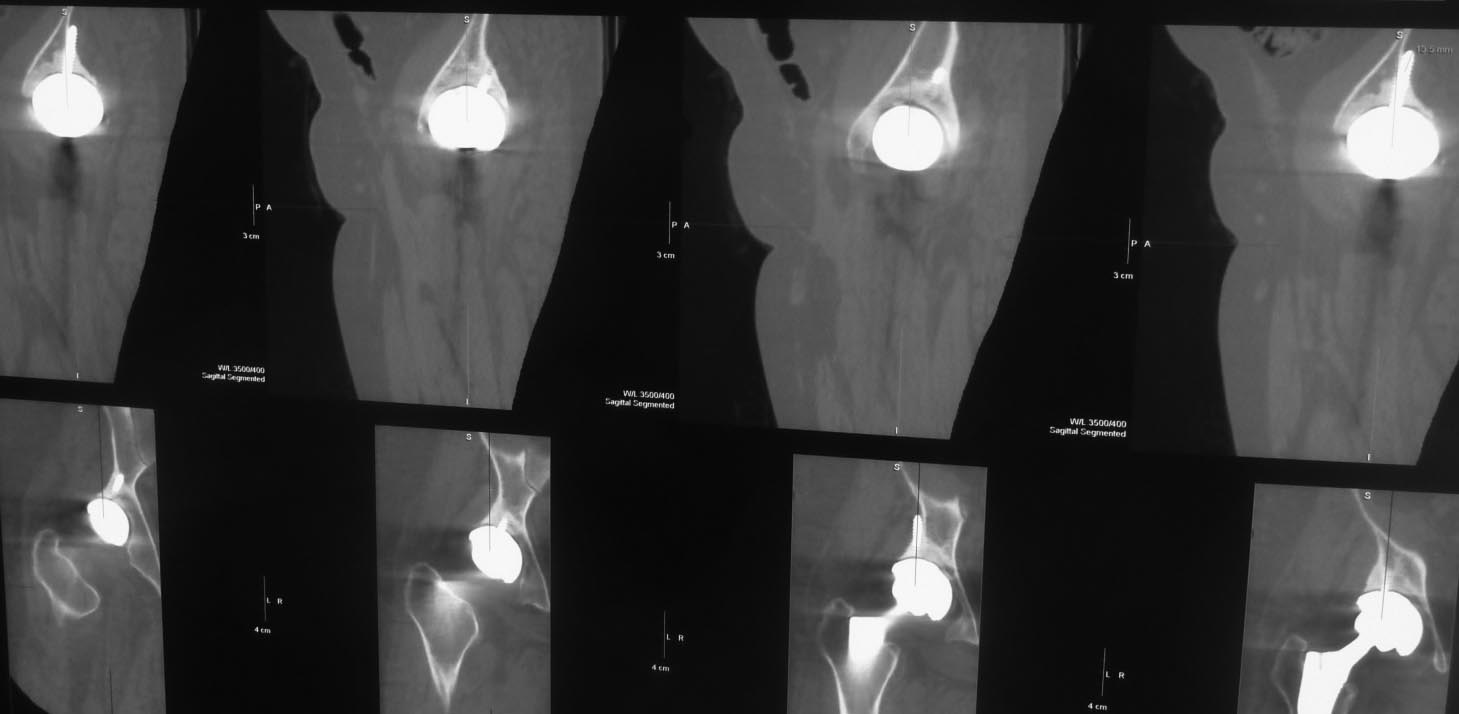

Пациент 58 лет оперирован 10 лет назад по поводу вывиха правого бедра с переломом головки. Во время открытого вправления был поврежден седалищный нерв (ягодичный доступ), по поводу чего впоследствии выполнены 3 вмешательства с неполным положительным эффектом. Через несколько месяцев после открытого вправления было осуществлено тотальное эндопротезирование.

Сейчас больше всего беспокоит стартовая боль, ходит с тростью, опираясь на нее 2 руками, ежедневно принимает нимесулид, хотя пытается убедить себя и окружающих, что, кроме стартовых, других болей нет. Резко ограничены движения в правом тазобедренном суставе, попытка ротации болезненна до крика. У невролога был - неврологическая патология отвергнута. Анализы крови нормальные, лихорадки нет. Казалось бы имеются все признаки нестабильности тазового компонента эндопротеза.

Вопрос: возможна ли нестабильность без рентгенологических признаков разрежения костной ткани вокруг винтов?

Уважаемый Сергей, у пациента имеются и клинические и рентгенологические признаки нестабильности чашки. Отсутствие резорбции вокруг винтов не должно Вас смущать. Ревизионное вмешательство однозначно показано.

Скорее всего нужно говорить о нестабильности вертлужного компонента. Есть разряжение вокруг чашки, которая скорее всего держится за счет винтов. Реэндоротезирование с заменой вертлужного компонента. Но перед операцией добиться получения пунктата на бакпосев, лучше даже 2 или 3 раза. Если есть инфекция то двухэтапное реэндопротезирование с применением цементного спейсора.

если винты сломаны на уровне чашки

Можно было начать с обычной рентгенограммы таза и простым анализом крови. Вместо КТ срезов, нужна прямая рентгенограмма таза, которая позволит сравнить уровень суставов и увидеть расшатывание вокруг ацетабулярного, а также бедренного компонентов. Сфокусированные КТ срезы, особенно 3Д не позволяют распознать вовлечение на уровне бедра и оценить артропластику в целом!

Спасибо за развернутый ответ. Но по поводу данного больного я задал единственный конкретный интересующий меня вопрос: возможна ли нестабильность вертлужного компонента при отсутствии признаков нестабильности фиксирующих чашку винтов? И именно для возможности ответить на этот вопрос представлены 3D срезы, позволяющие точнее оценить расположение винтов.К сожалению, на интересующий меня вопрос вы не ответили. А про результаты обычных анализов крови я написал, они в пределах нормы. И обычные рентгенограммы таза с захватом обеих ног пациенту сделаны. К ним у меня нет вопросов.